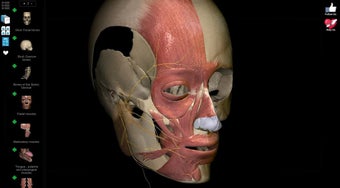

Anatomy Learning - 3D Atlas è un'app gratuita per Android che appartiene alla categoria Medicina ed è stata sviluppata da AnatomyLearning. È consigliata per principianti, studenti di medicina, apprendisti visivi, professionisti medici, medici.

Questa app è meglio conosciuta per le seguenti caratteristiche e qualità: strumento di studio, apprendimento dell'anatomia, strumento di apprendimento e riferimento di base.

La gente dice sono a scuola per radiografia e sono un apprendista piuttosto visivo, bella app per principianti, incantevole per gli appassionati di fitness.